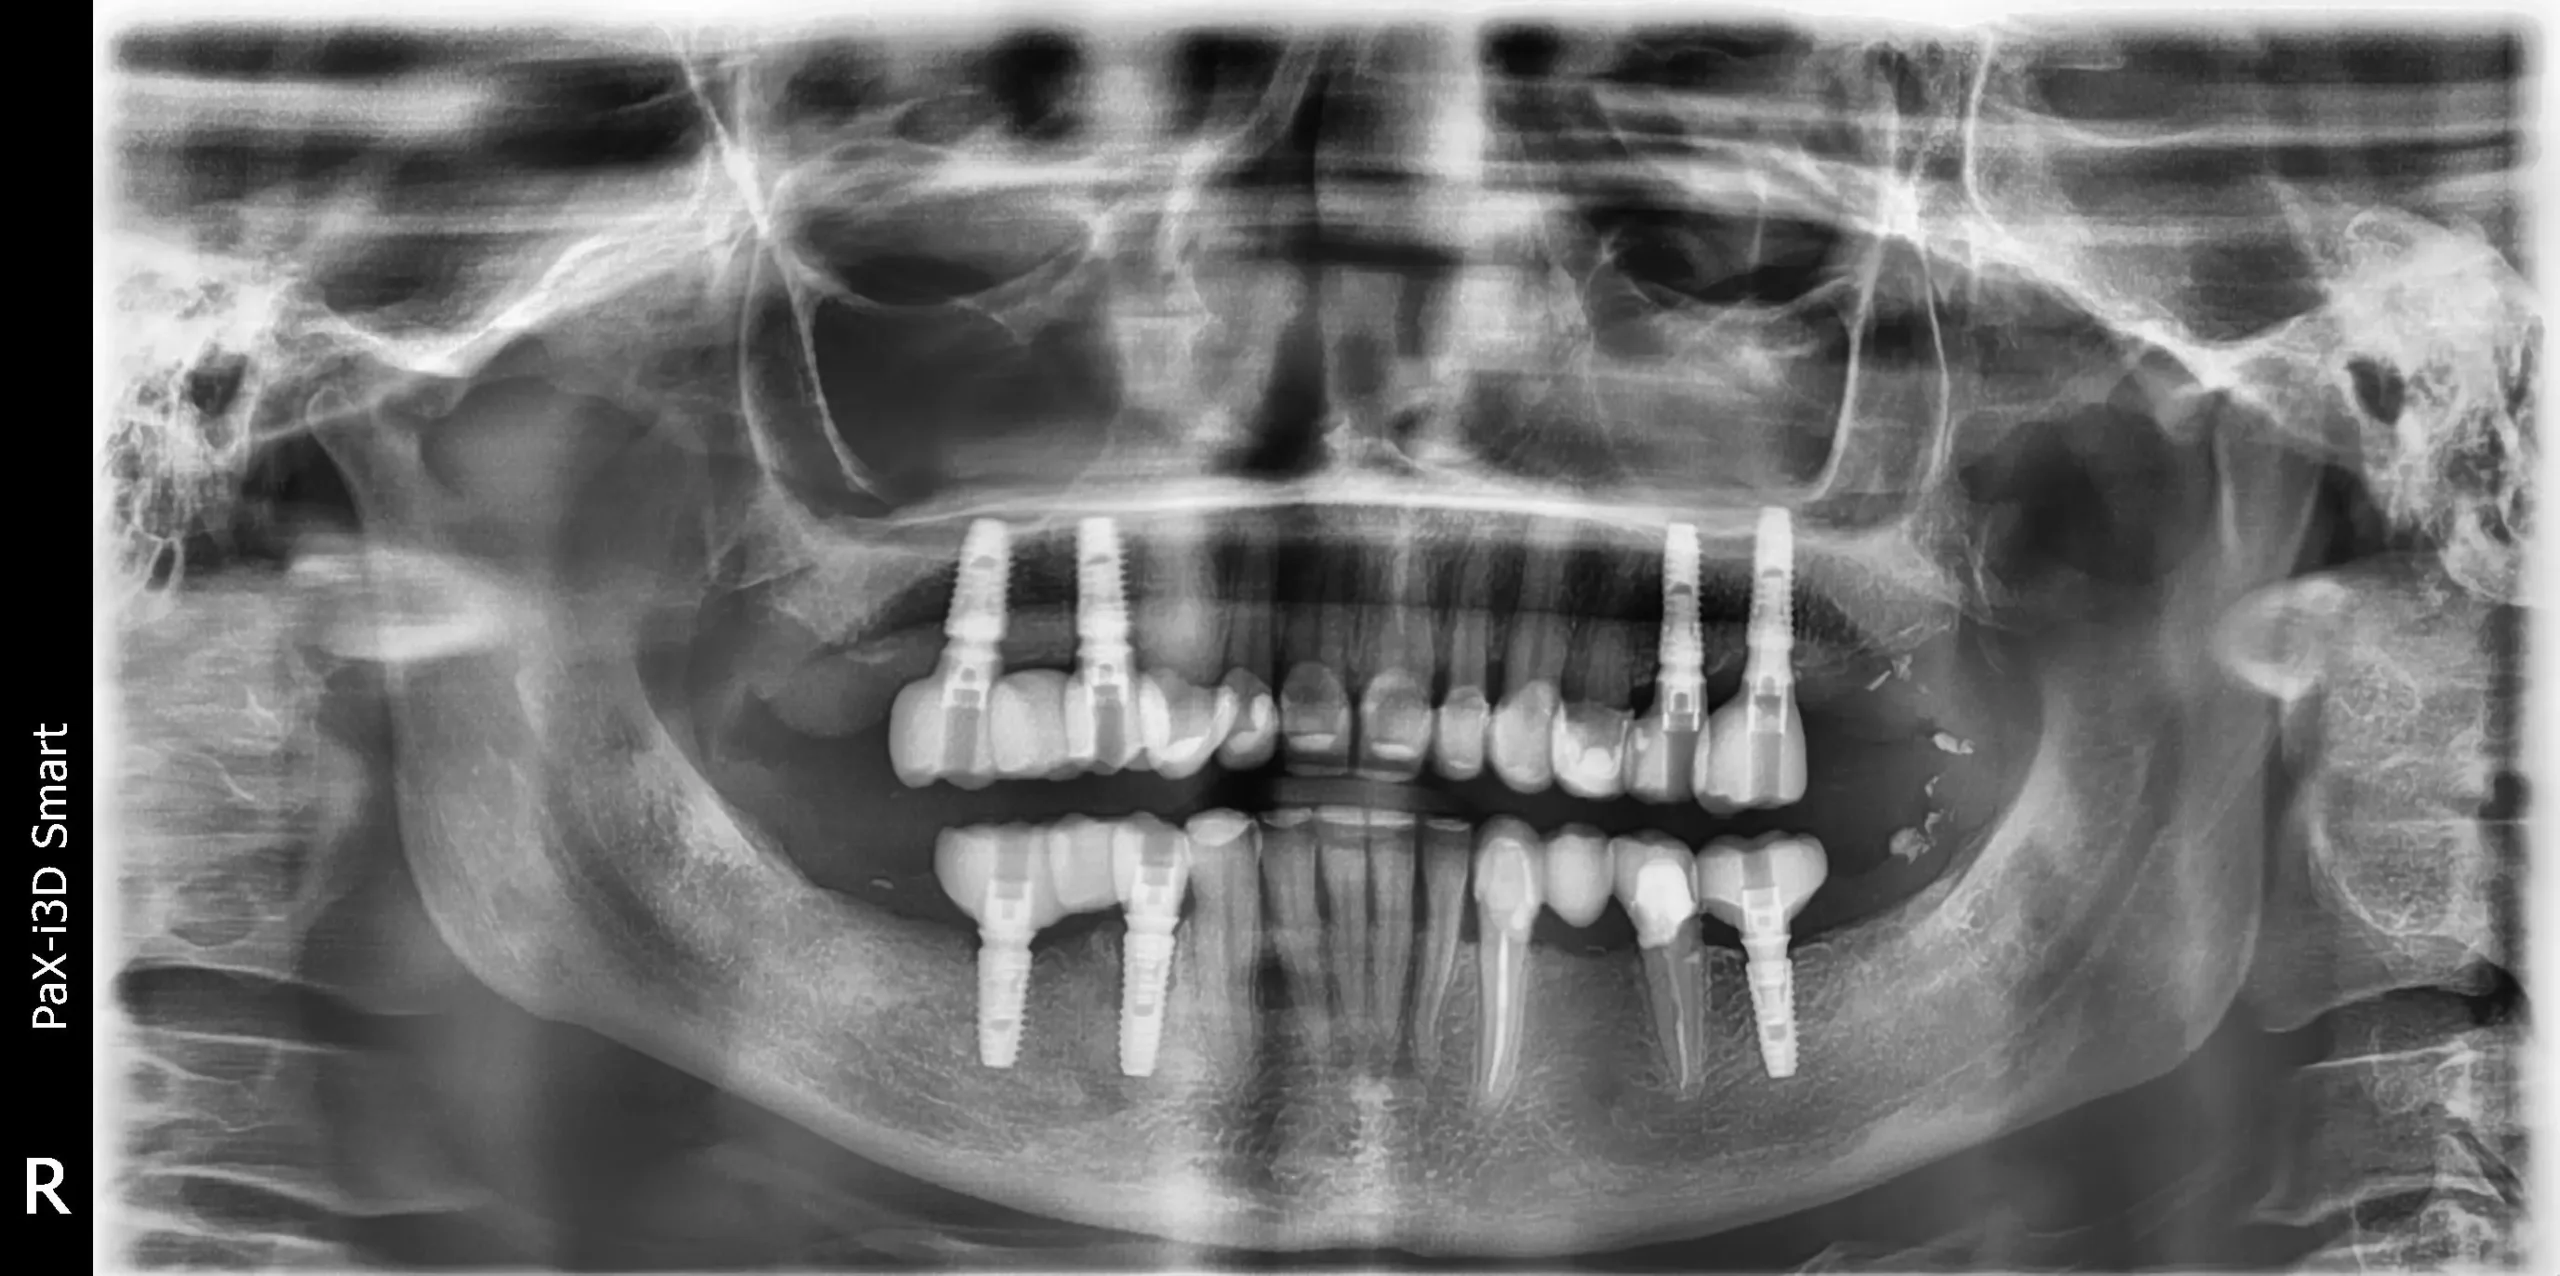

Diagnóstico Diagnóstico

1. Destrucción del esmalte dentario

2. Inflamación gingival

3. Ausencia de mordida funcional

Solución Solución

Saneamiento de encías y hueso

Colocación de coronas de cerámica sobre dientes naturales

Colocación de implantes dentales

Sustitución de puentes antiguos

Tratamiento de conductos (endodoncia)